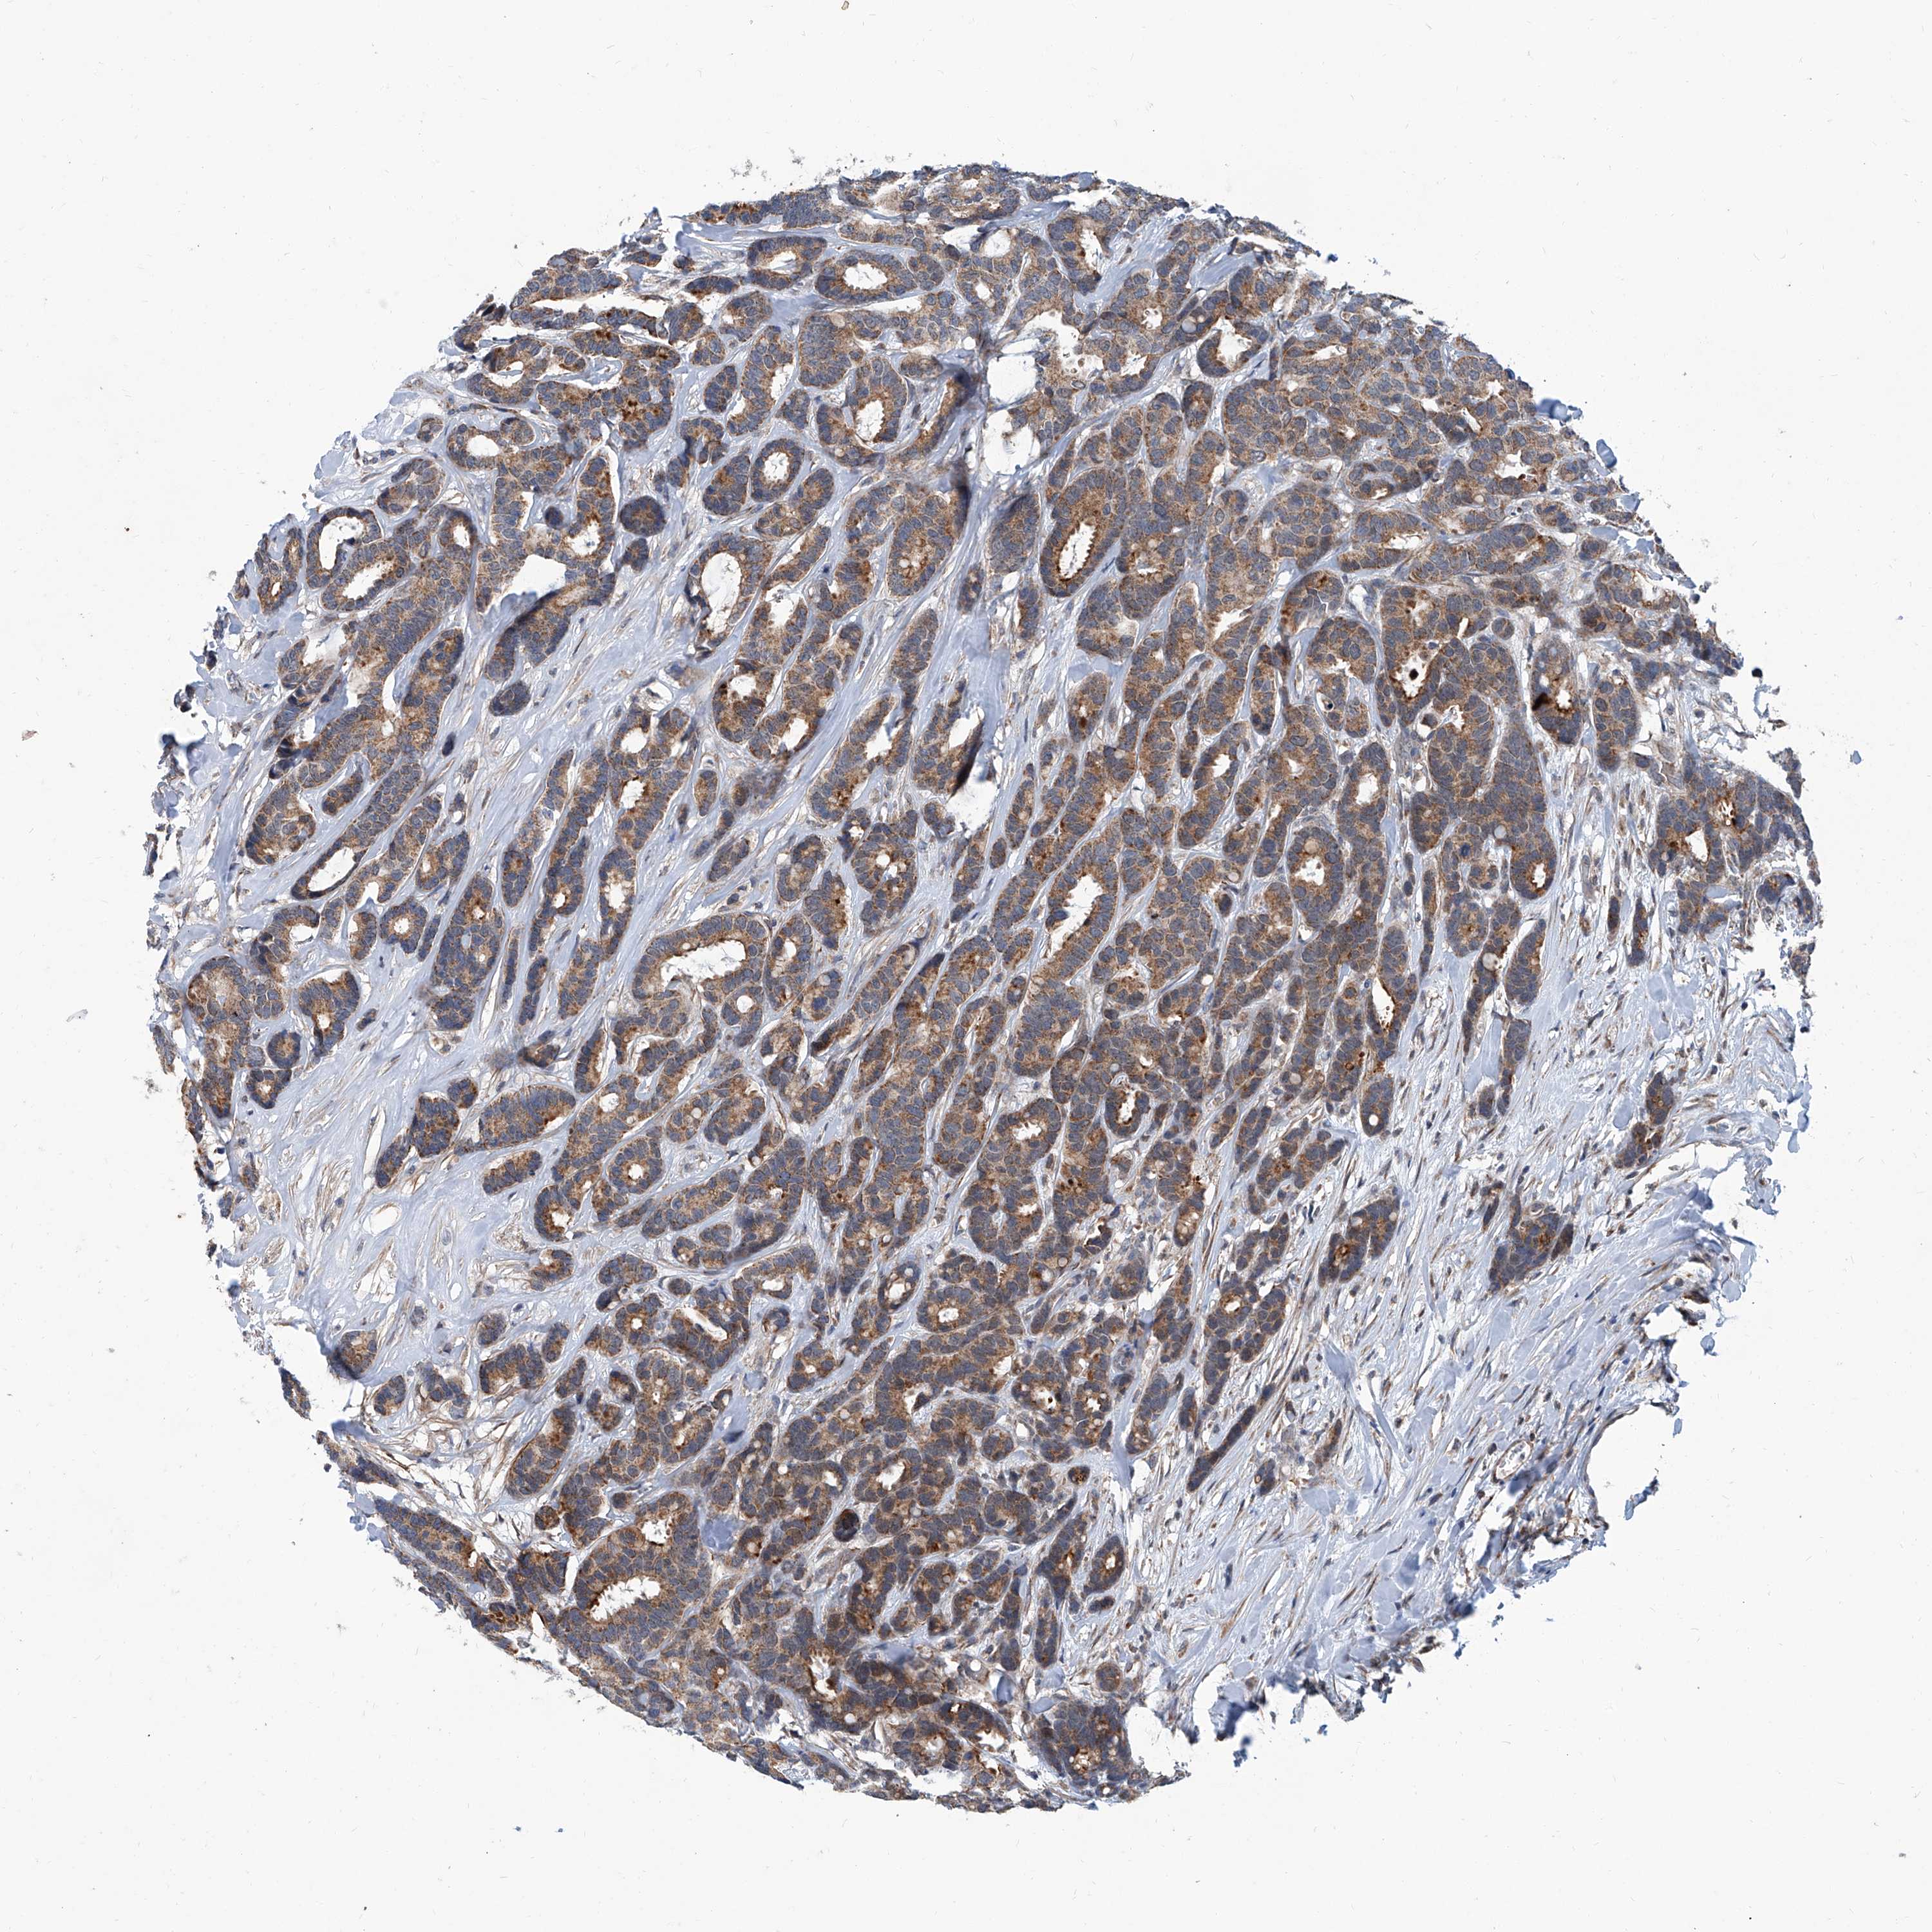

CANCER BREAST CANCER Show tissue menu

BRCA TCGA BRCA VALIDATION PROTEIN EXPRESSION